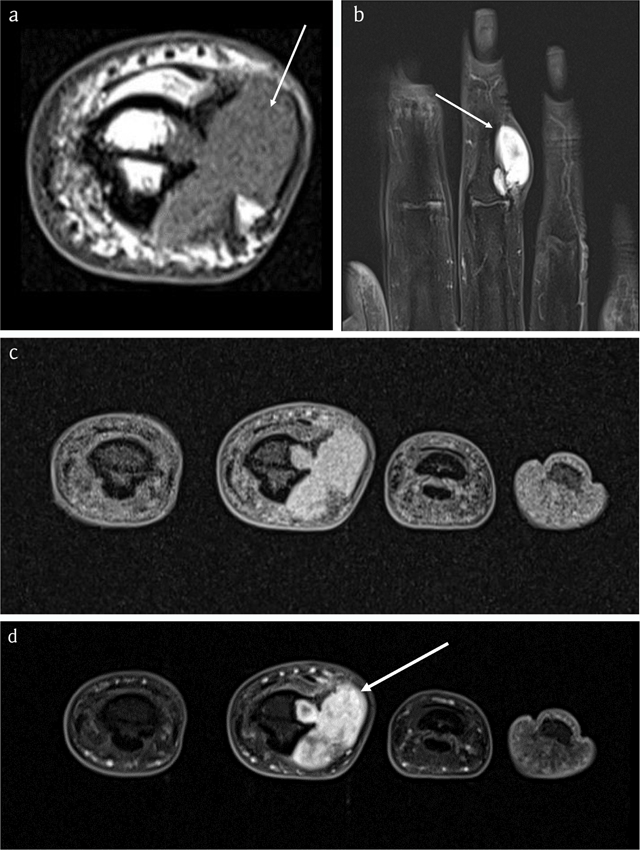

Figure 7

Case 2 – MRI. Axial T1-WI (a). Coronal FS T2-WI (b). Axial FS T1-WI (c). Axial FS T1-WI after administration of gadolinium contrast (d). The lesion is isointense to muscle (arrow in a) and hyperintense on FS T2-WI (arrow in b) with ring-and-arc enhancement (arrow in d), in keeping with chondroid matrix.